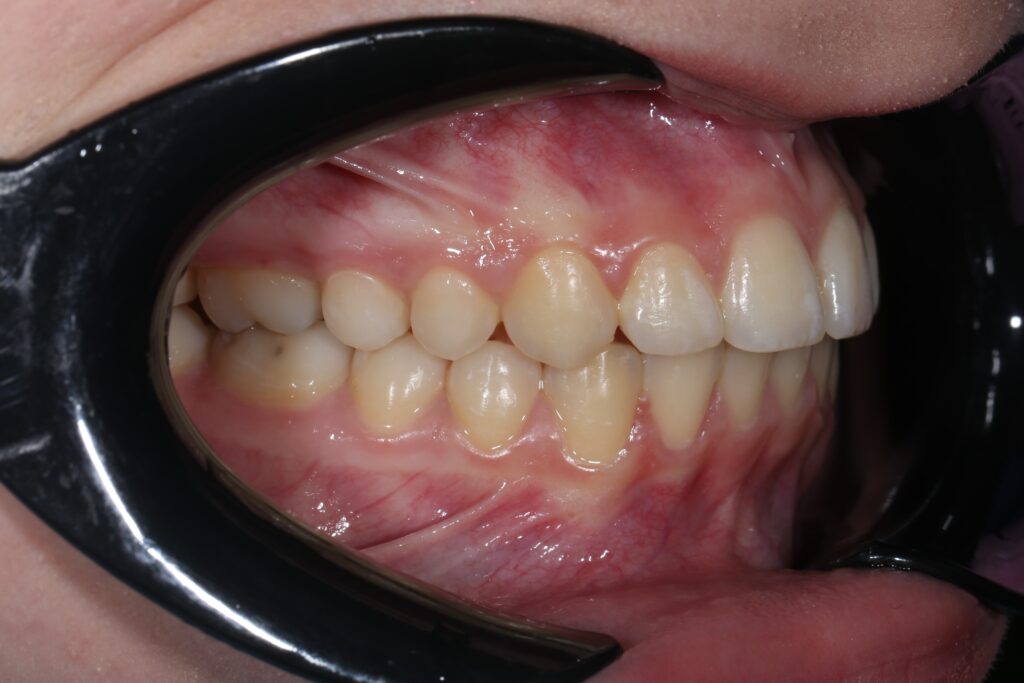

Результаты

результат лечения брекет-системой